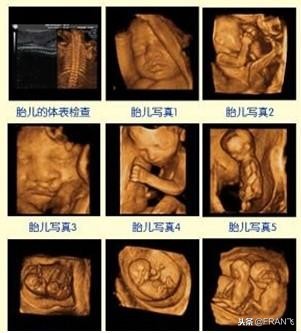

四维彩超的全称为四维彩色超声诊断仪,是世界上最先进的彩色超声设备。第四维是指时间这个矢量,所以也被称作实时三维。四维彩超能够表面成像,能更清晰地查出来胎儿的唇腭裂、四肢发育畸形、脑膜膨出、脊柱裂、腹壁裂等先天畸形。

四维彩超能够直观地看到胎儿在母体内的活动状况,根据活动情况来判断胎儿的发育是否良好,一般来说,四维彩超是从胎儿面部畸形、神经系统、消化系统、泌尿系统、其它畸形几个方面来检查的,通过四维彩超,可以检查出来胎儿是否有唇腭裂,是否脑积水、脊柱裂,内脏外翻、肾积水、尿道梗阻、羊水过多等问题。